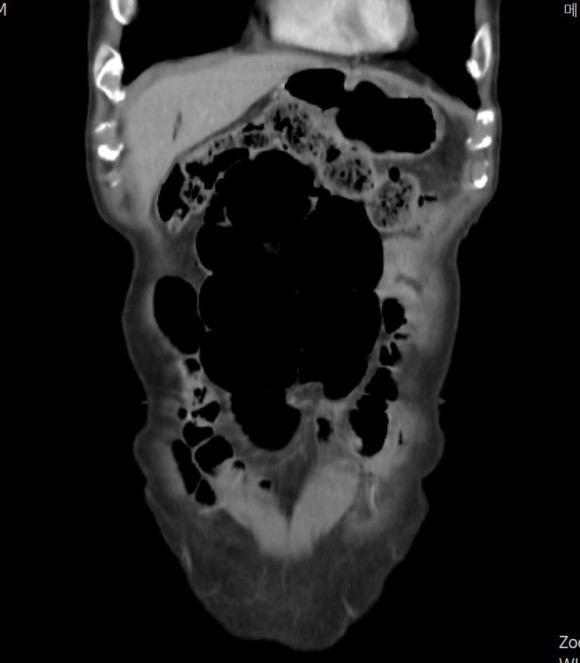

위의 복부 ct에서 시커멓게 보이는 부분이 위와 장에 차 있는 공기다. 이런 공기는 거의 모르는 사이에 공기를 먹고 들어온 것이다. 오른쪽 사진이 배꼽 근처인데 공기 때문에 배가 불렀다. 필자가 진찰을 할 때는 배가 부른 소견이 없었다.